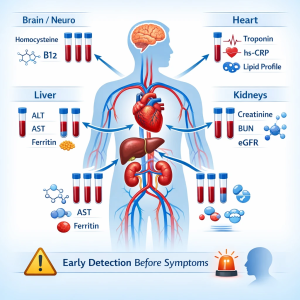

نشانگرهای بیوشیمیایی مرتبط با آسیب زودهنگام اندامهای حیاتی

۳. قلب و عروق؛ هشدارهای زودهنگام در خون

بیماریهای قلبی اغلب از عروق شروع میشوند.

نشانگرهای مهم:

- LDL بالا یا HDL پایین

- تریگلیسرید بالا

- افزایش hs-CRP (التهاب عروقی)

- افزایش خفیف تروپونین در شرایط خاص

این تغییرات نشاندهنده افزایش خطر بیماری قلبی حتی در افراد بدون علامت هستند.

۵. مغز و سیستم عصبی؛ آسیبهای متابولیک پنهان

برخی اختلالات عصبی ریشه بیوشیمیایی دارند.

نشانگرهای مهم:

- کمبود ویتامین B12

- افزایش هموسیستئین

- اختلالات تیروئیدی (TSH غیرطبیعی)

این تغییرات میتوانند پیشزمینه اختلالات شناختی، افسردگی یا نوروپاتی باشند.